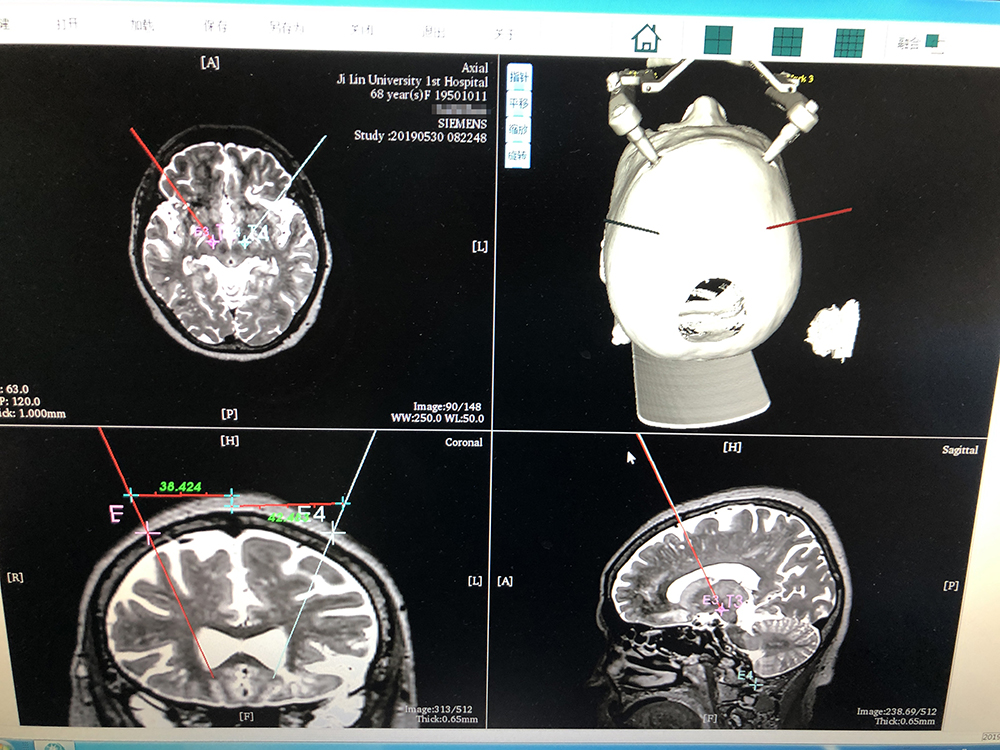

術前,邱吉慶教授借助“睿米”神經(jīng)外科手術機器人配套軟件,為患者制定雙側(cè) STN 核團植入電極的手術路徑規(guī)劃。

借助“睿米”軟件制定手術規(guī)劃